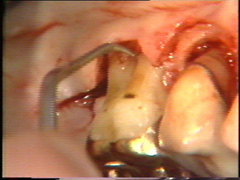

Las superficies de la raíz se limpian (raspado y alisado radicular) cuidadosamente y el tejido de granulación en los defectos óseos (cráter) es eliminado. En la superficie bucal del segundo premolar hay  un cráter óseo y cálculo en la supericies dental adyacente.

El cálculo del segundo premolar  está unido firmemente a la superficie dental y es un proceso tedioso el quitarlo.

En las zonas dónde están las lesiones de furcación es dificil su limpieza: Puede utilizarse instrumental de mano, ultrasonido y a veces debe modificar la anatomía de la lesión para mejorar la higiene postoperatoria. Esto lo puede llevar a cavo con instrumental rotatorio (puntas de diamante) a baja velocidad y abundante refrigeración acuosa.

En la superficie palatina del central, hay un defecto grande en la superficie de la raíz. Probablemente sea una fractura que ocurrió en relación con el accidente. El tejido de  granulación se  ha formado en el defecto que se limpia completamente. Postoperatoriamente es necesario poner apicalmente el colgajo en relación con el defecto de la raíz  para crear una condición higiénica manejable